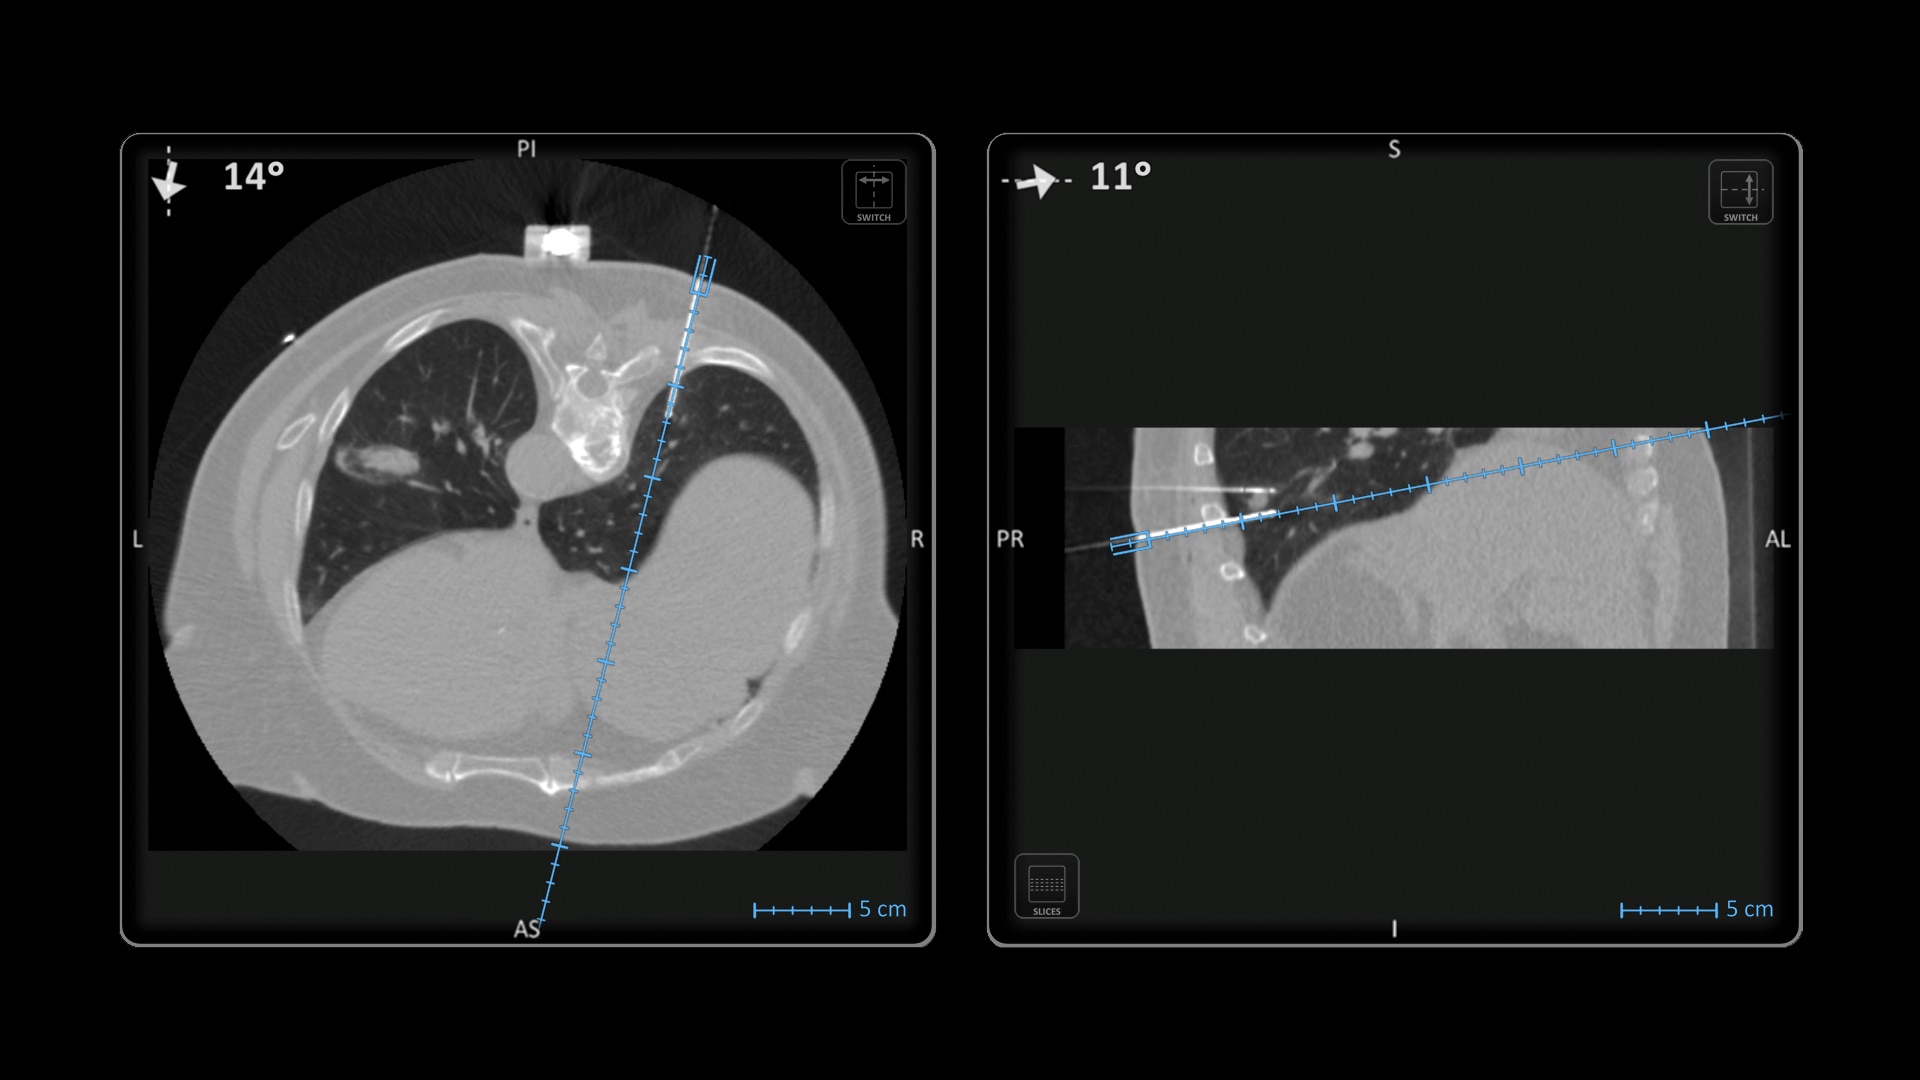

Versatility

Ideal to use with various percutaneous interventions² with various complexity